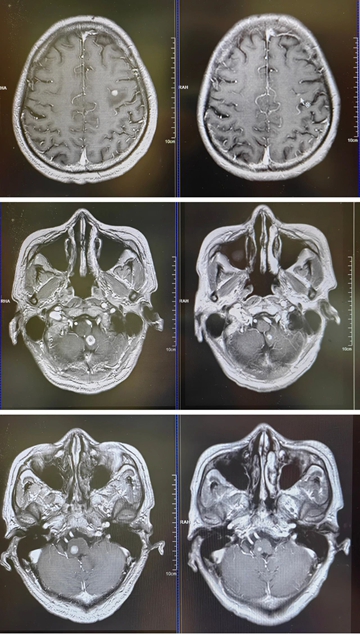

5月3日,今年五一假期期间,在肿瘤·血液病科忠山病区进行前期新辅助治疗的肺癌患者再次入院。主管医生张林松医生第一时间准确地抓住病情信号——高度怀疑肿瘤脑转移,并催促赶紧做头部MRI。结果显示:3颗转移瘤已悄然在颅内“安营扎寨”。

3颗肿瘤位置分散且刁钻,既要彻底清除,又不能伤及周围正常脑组织。伽玛刀团队根据脑转移瘤病灶大小、数目、位置、放射敏感性和患者一般情况来进行综合评估,定下“分两次治疗”的方案。

计划室内,伽玛刀团队医生精准勾勒肿瘤轮廓,8天后,3颗肿瘤纷纷“缩水”,转回肿瘤·血液病科忠山院区。

两个周期下来,一颗肿瘤彻底基本消失,另外两颗缩小一多半,化验单上的各项指标全部正常。